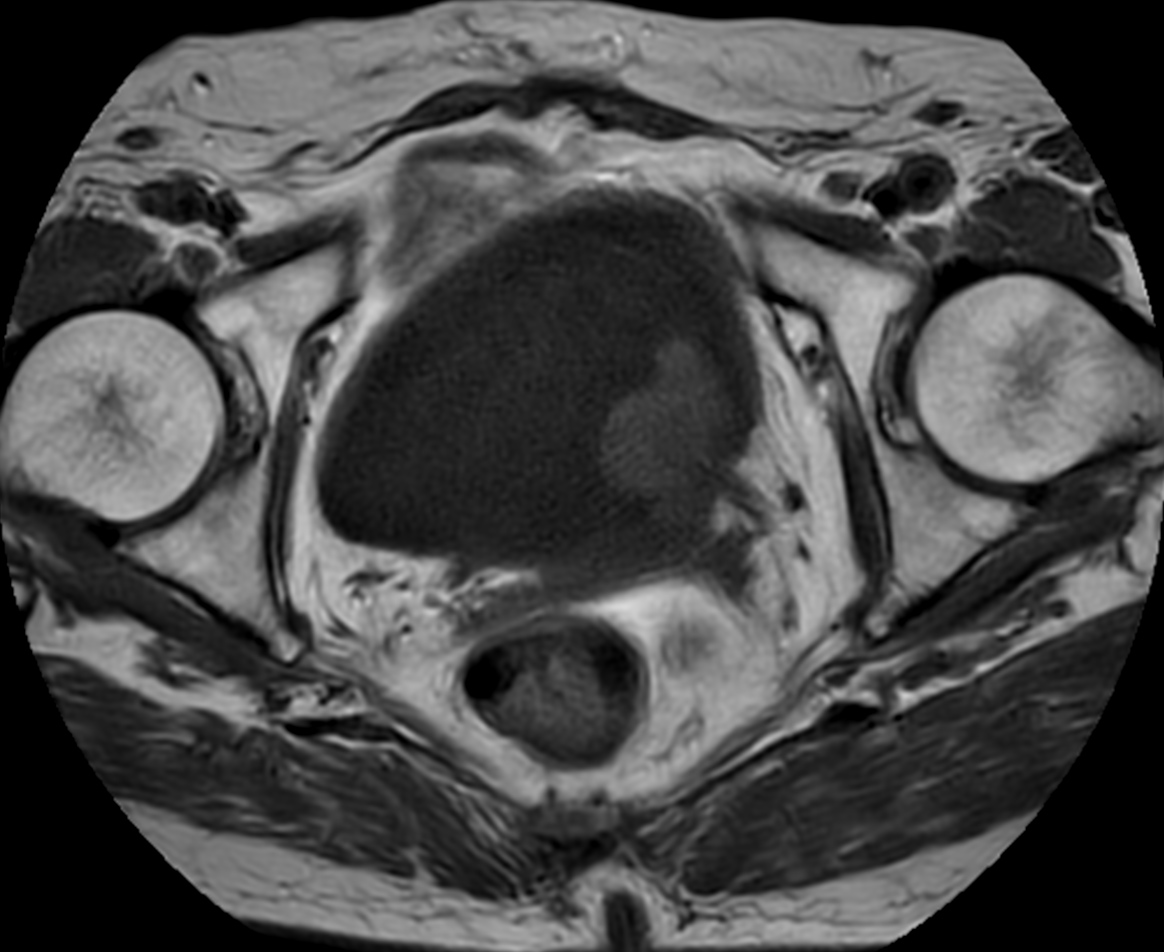

Patient with bladder cancer. The ExamCard includes techniques for motion reduced imaging (MultiVane XD), 3D TSE imaging (PelvisVIEW) allowing for multiple image directions in one single scan, a multi-phase contrast-enhanced sequence (4D FreeBreathing) to improve imaging confidence and Compressed SENSE to accelerate the entire exam.

T2w TSE MultiVane XD